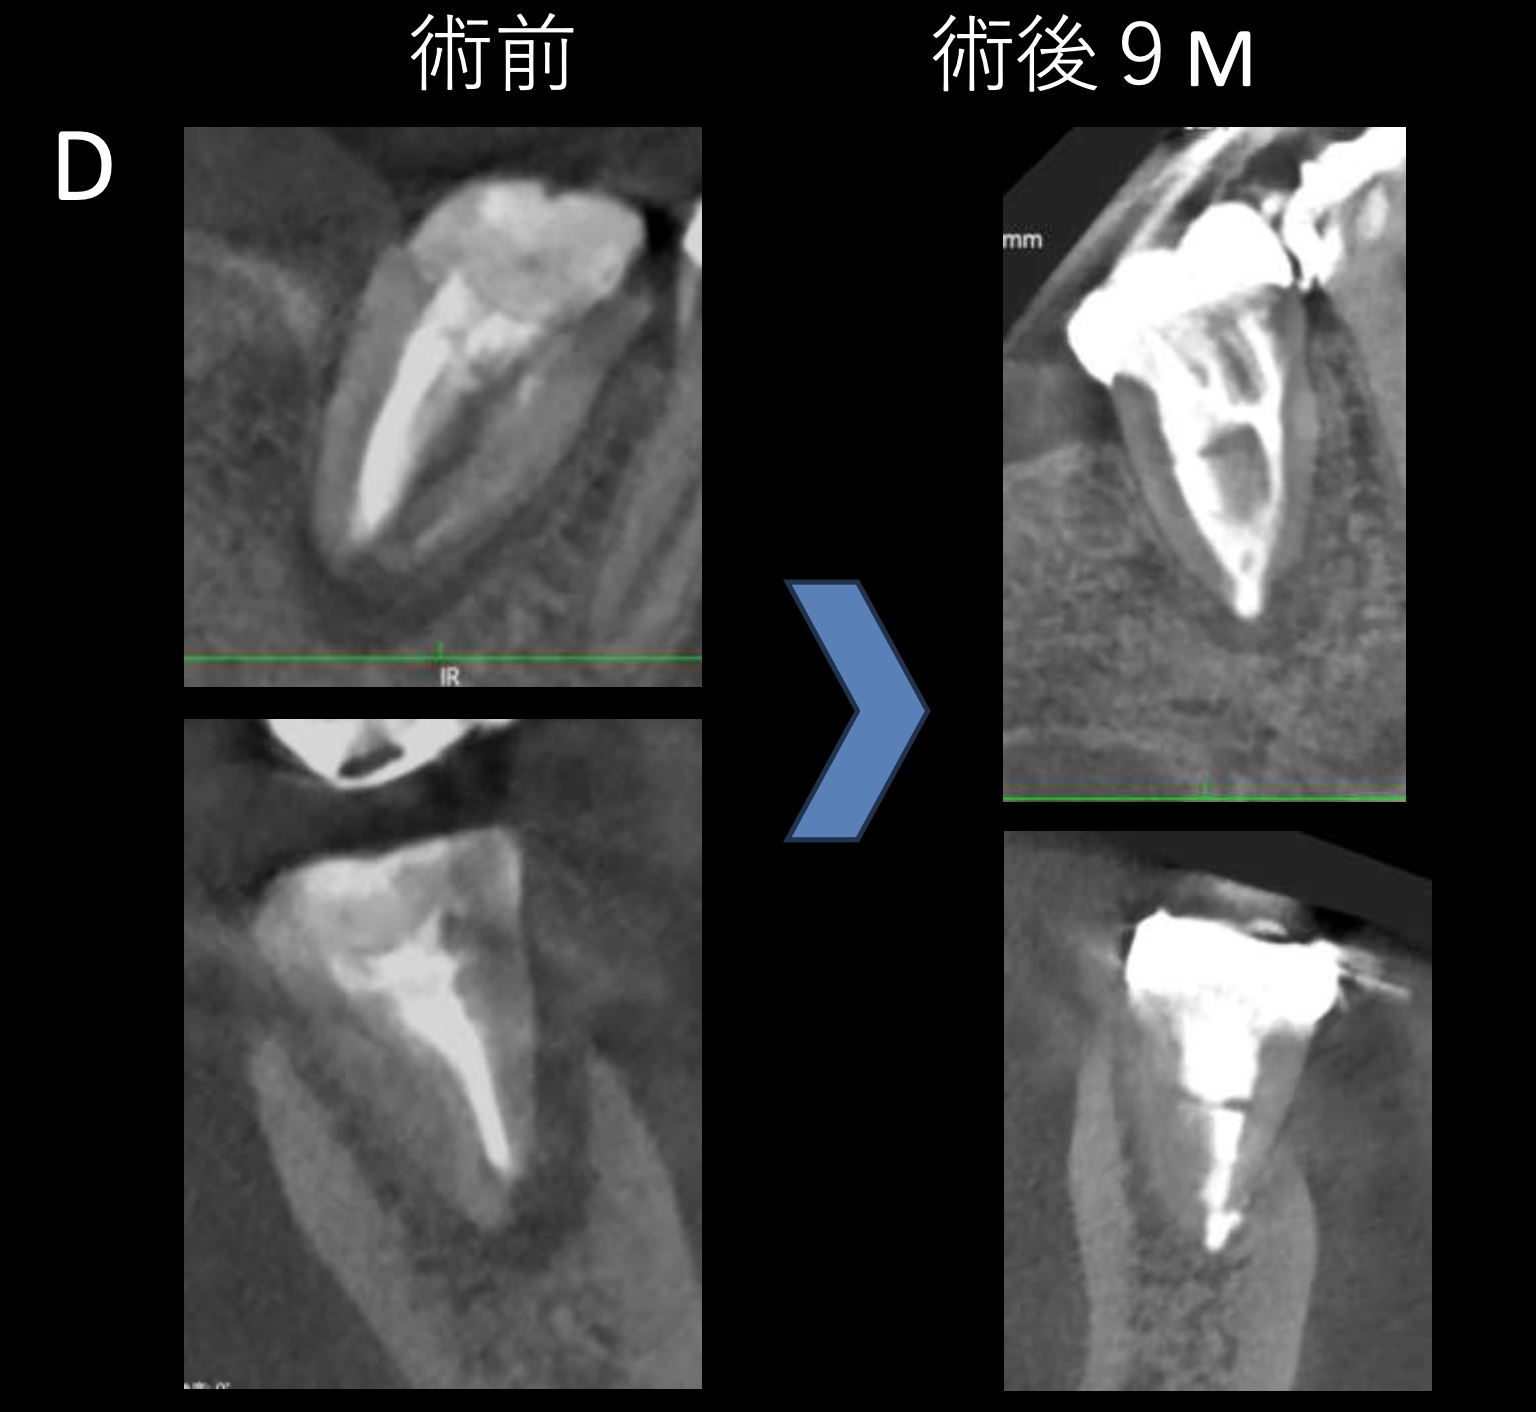

#7がCold testに無反応である。

故に、#7,8の非外科的根管治療を行うことになった。

が、#8のメタルコアは外しにくいだろう。

CBCTでは2本とも口蓋側の皮質骨が消失している。

という絶望的な状況である。

が、

術前にその予後を患者さんに説明し、

治療へ移行した。

その結果、

ここから4ヶ月が経過すると…

臨床症状も皮質骨も大きく治癒している。

1年後の予後が気になるところであるが、すごくよくマネージメントできているだろう。